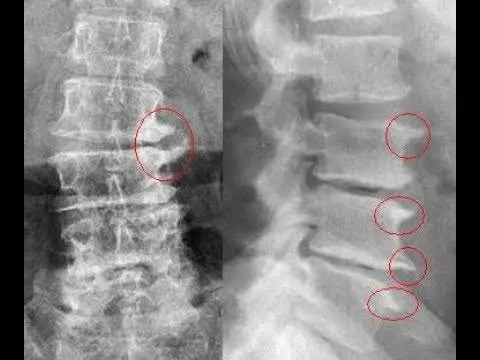

Radiografia de um bico de papagaio

Radiografia de um bico de papagaio.

Até aqui você já sabe que a hérnia de disco é quando o disco sai do seu lugar e começa a pinçar o nervo mais próximo. E que em alguns casos, como na osteoartrite esses discos diminuem de tamanho o que desestabiliza nossa estrutura.

Pois bem, o bico de papagaio é uma formação de ossos nas vértebras que servem para compensar o espaço perdido pelo que quer que tenha diminuído os espaços onde ficam os discos.

O exame solicitado pelo médico no primeiro momento é o RX, que não mostra se há uma hérnia de disco, mas pode observar as estruturas da coluna e como estão as vértebras, descartando fraturas ou tumores.

Nesse exame o profissional observa o espaço entre uma vértebra e outra além os bicos de papagaio.